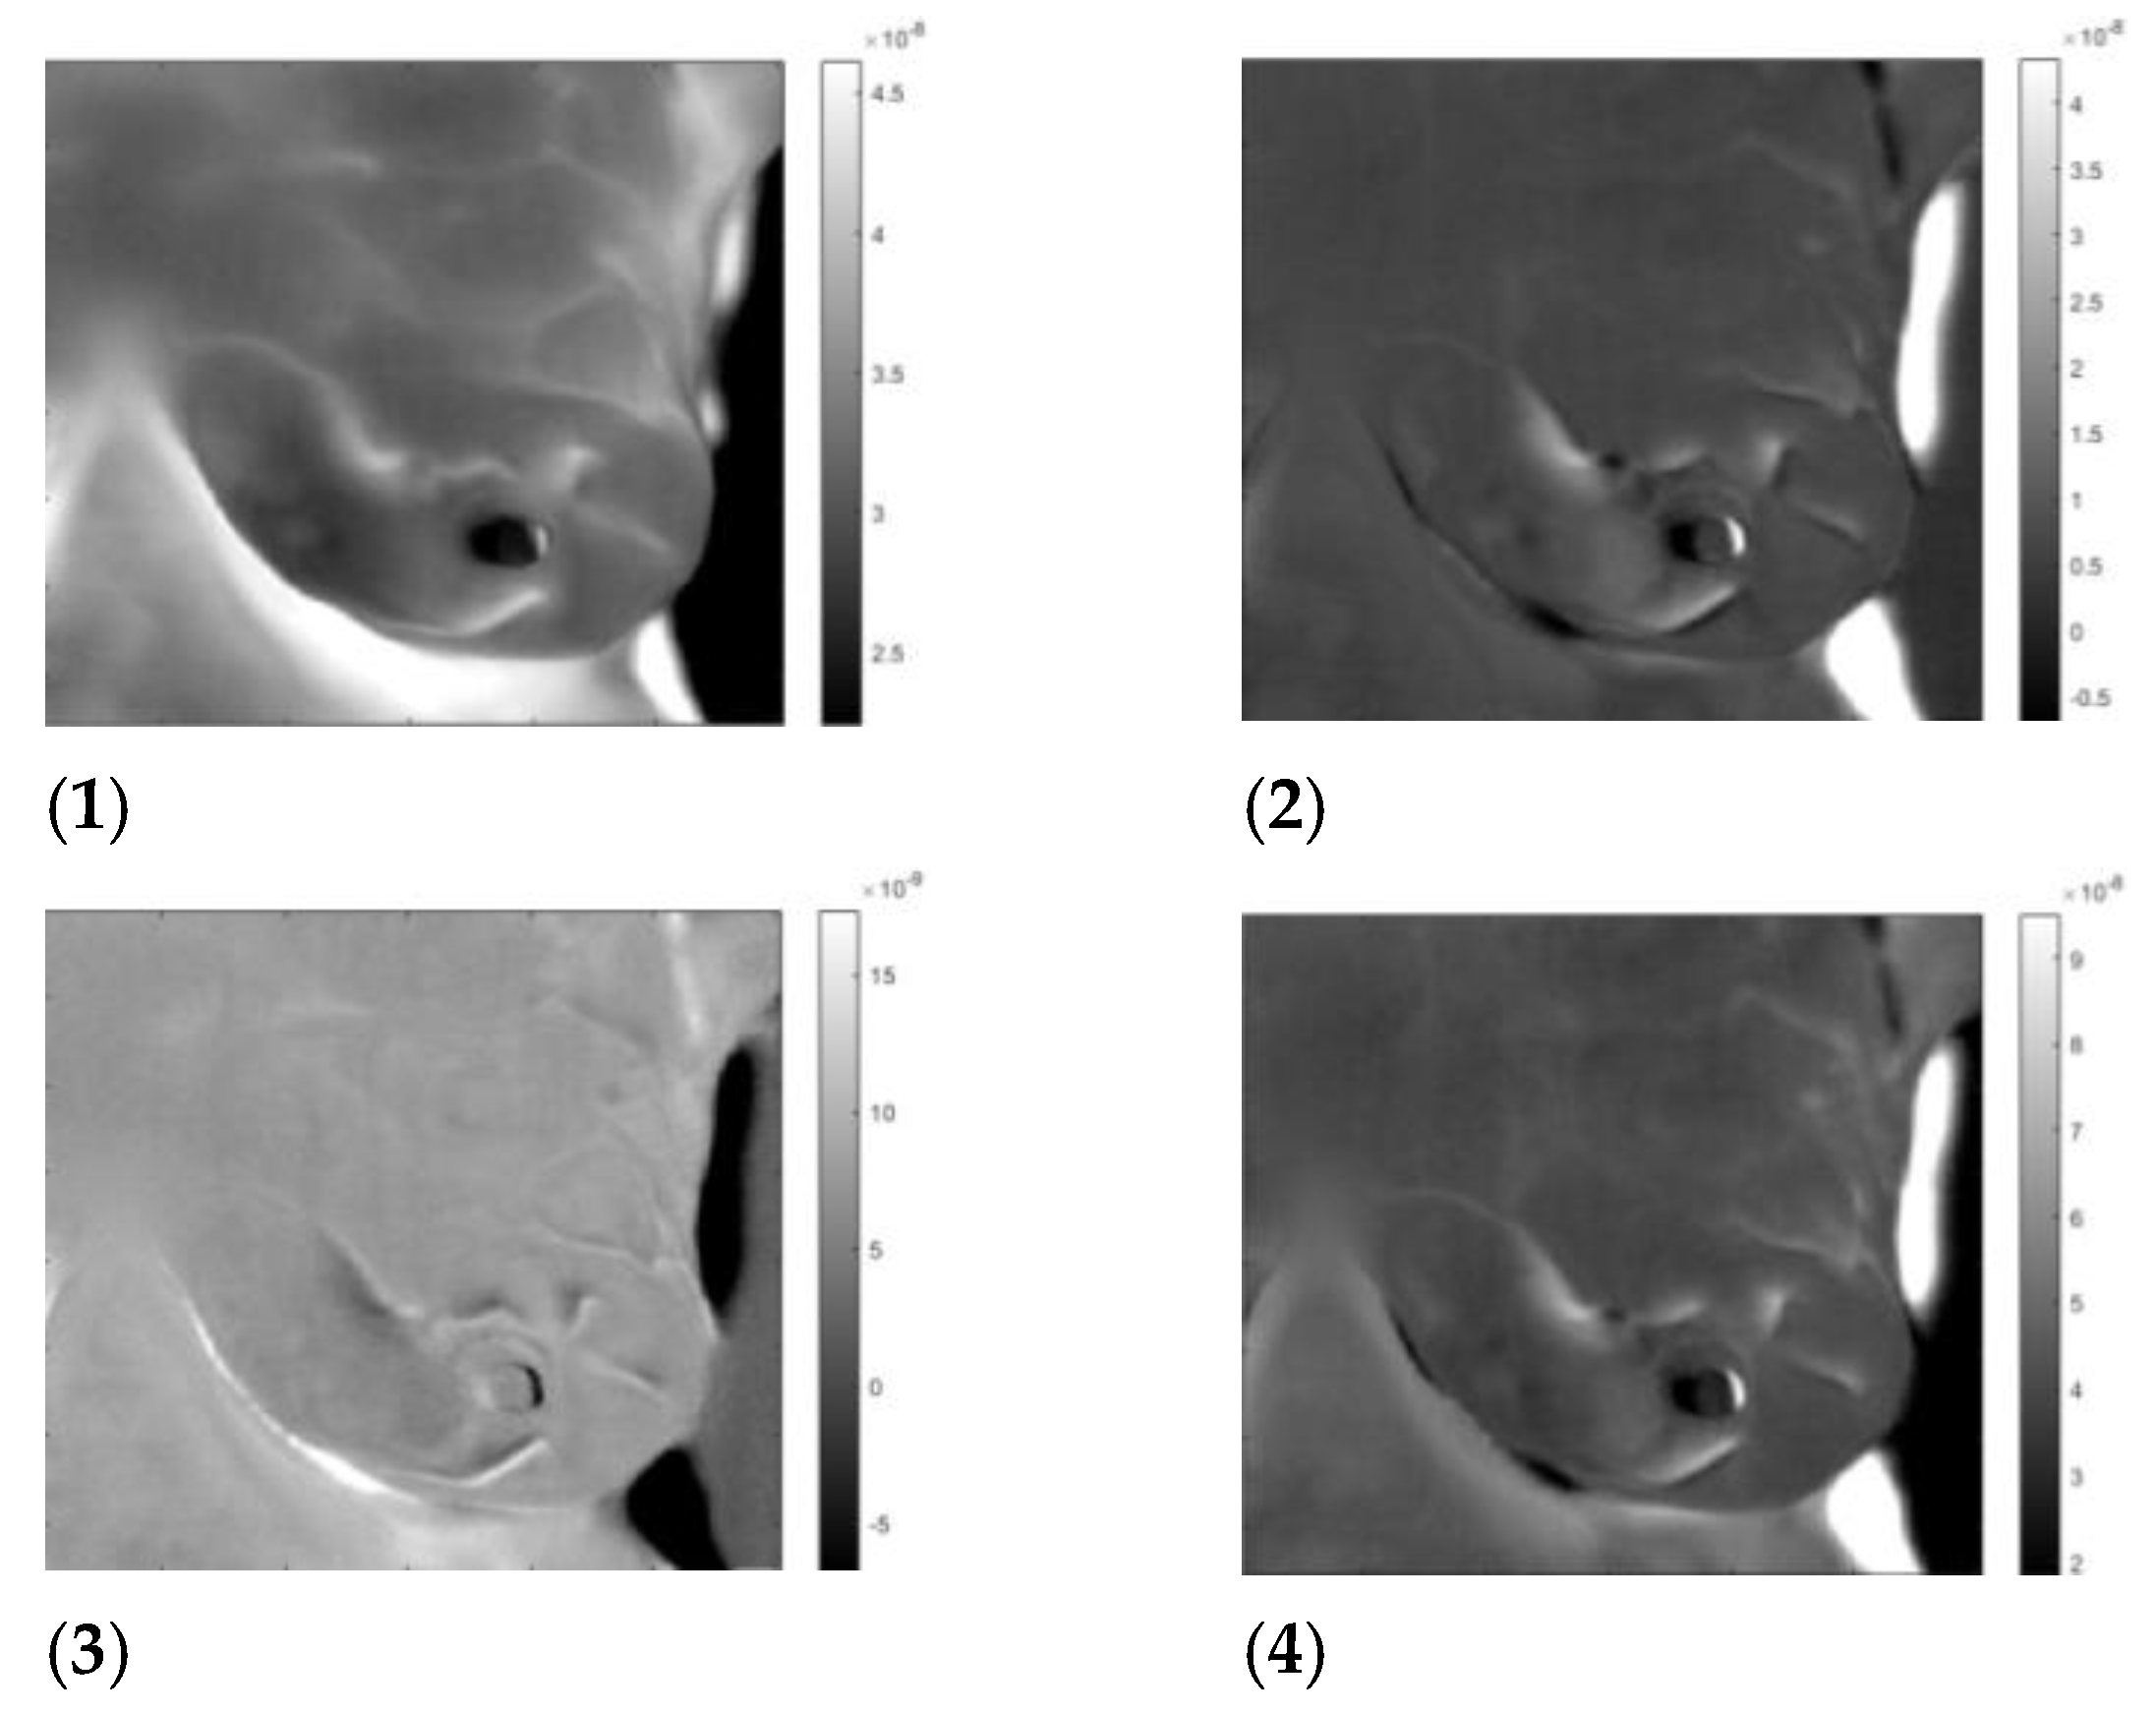

3. Results

3.3. Analysis